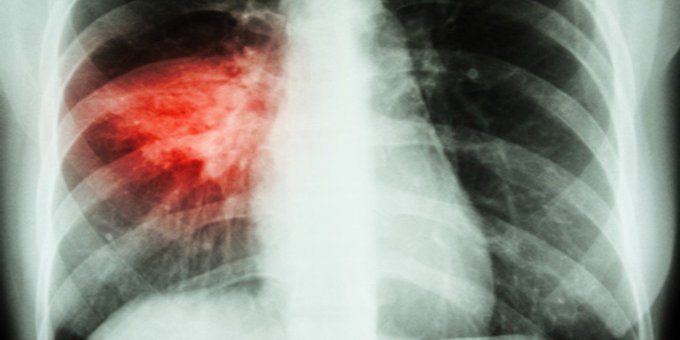

¿Cuáles son los tipos de #neumonía que existen y cuáles son sus síntomas más comunes? En el Día Mundial de la Neumonía entérate aquí ow.ly/6lgQ50x8yVZ #WorldPneumoniaDay